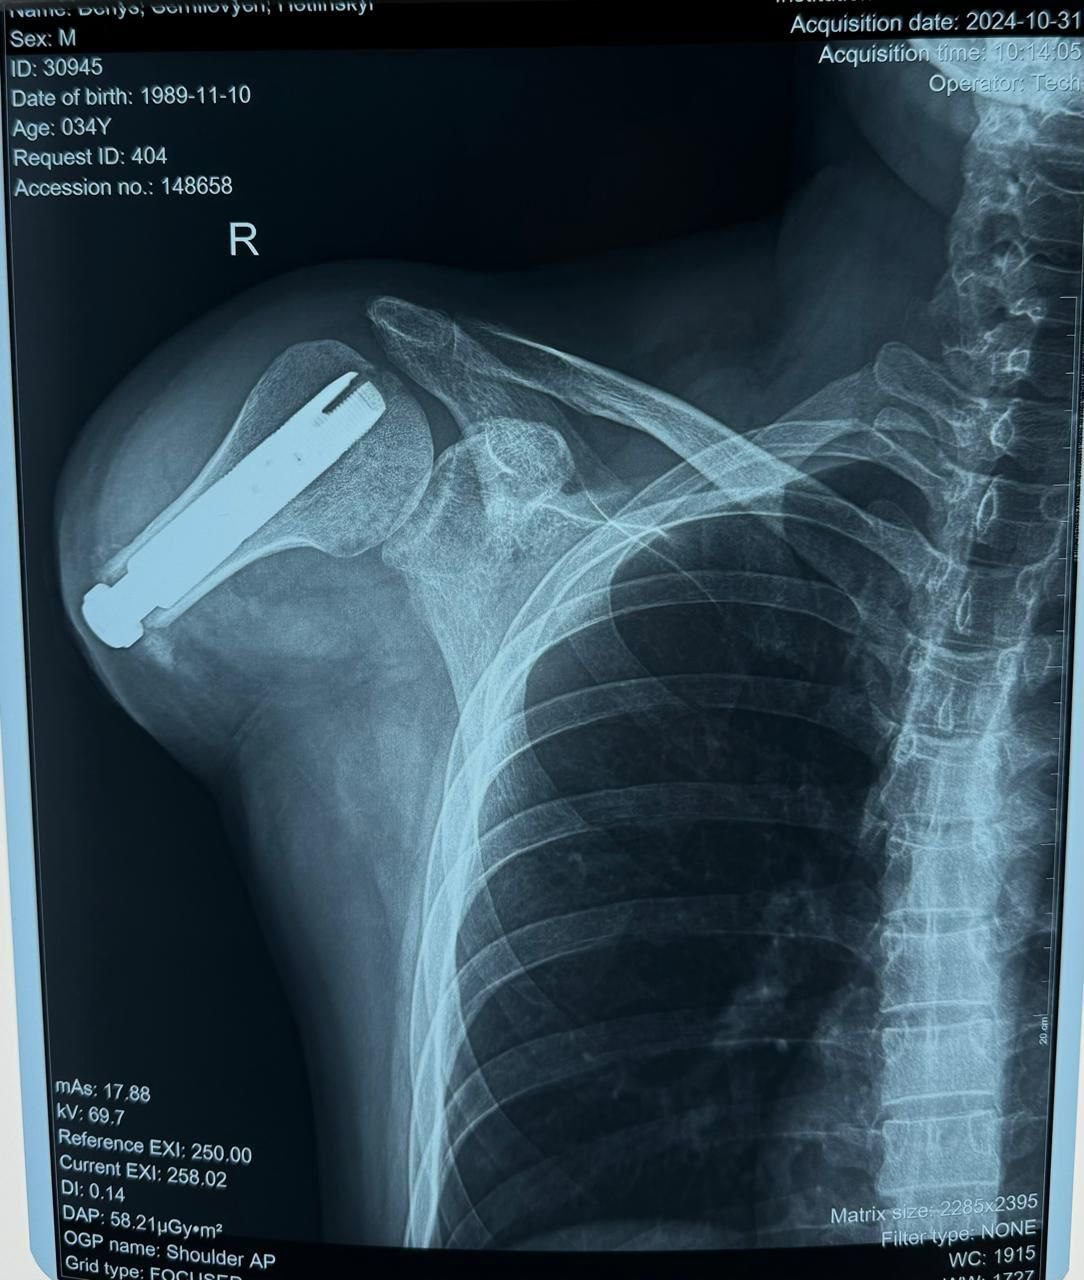

TYTANOVI – це сучасний реабілітаційний центр України, який спеціалізується на найскладніших випадках протезування та допомагає постраждалим воїнам відновити себе не тільки фізично, а й морально. Заклад надає допомогу пацієнтам з високими ампутаціями, яким часто відмовляють інші реабілітаційні центри. У рамках співпраці з Respublika Park центр отримує фінансування для проведення високотехнологічних операцій з остеоінтеграції, вартість кожної з яких складає близько 23 тисячі євро.

Наш центр працює з найскладнішими випадками ампутацій, часто беручись за ситуації, від яких відмовляються інші реабілітаційні заклади. Завдяки підтримці Respublika Park ми можемо продовжувати надавати високотехнологічну допомогу. Сучасні технології остеоінтеграції дають шанс на повноцінне життя навіть у найскладніших випадках, – прокоментував В'ячеслав Запорожець, засновник центру TYTANOVI.